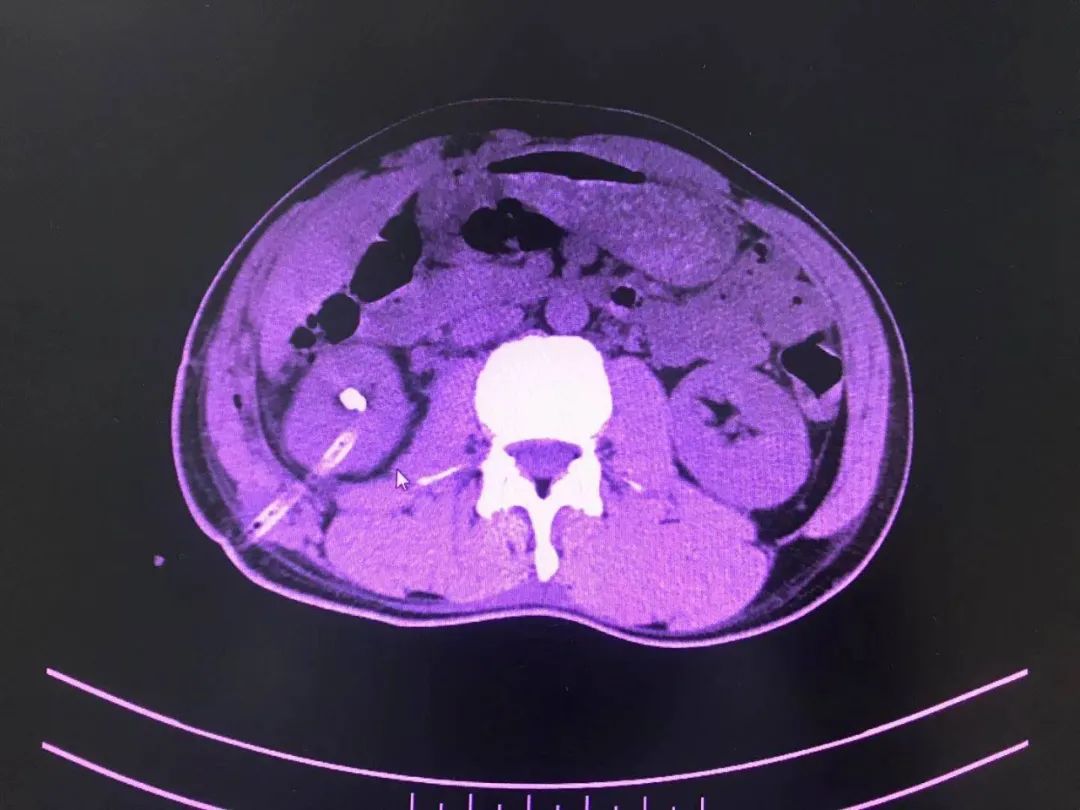

今年1月,医院外一科收治了一名40多岁的男性患者。该患者因腰部绞痛难忍,前来医院就诊。以刘文庭医生和尹曦医生为代表的外一科团队在对病人查体后发现,患者右肾结石散在且多发,结石密度影,肾实质厚,肾囊肿巨大且多发,手术难度颇大。

经过外一科医护团队对患者病情的仔细分析和详细论证,终于设计出一条适合患者病情的风险最小的手术治疗方案,即经皮肾囊肿输尿管软镜下右肾结石钬激光碎石术;利用此技术,将患者复杂性肾结石和肾囊肿通过同一通道经皮肾贯穿囊肿先内引流,再由内引流孔进入肾盂,最后利用钬激光进行碎石。患者利用此新技术前后共进行了两次碎石手术,手术治疗效果良好。第二次碎石手术顺利完成后,患者体内95%的结石碎石成功并成功排除体外,其病情已得到明显好转,目前已康复出院。